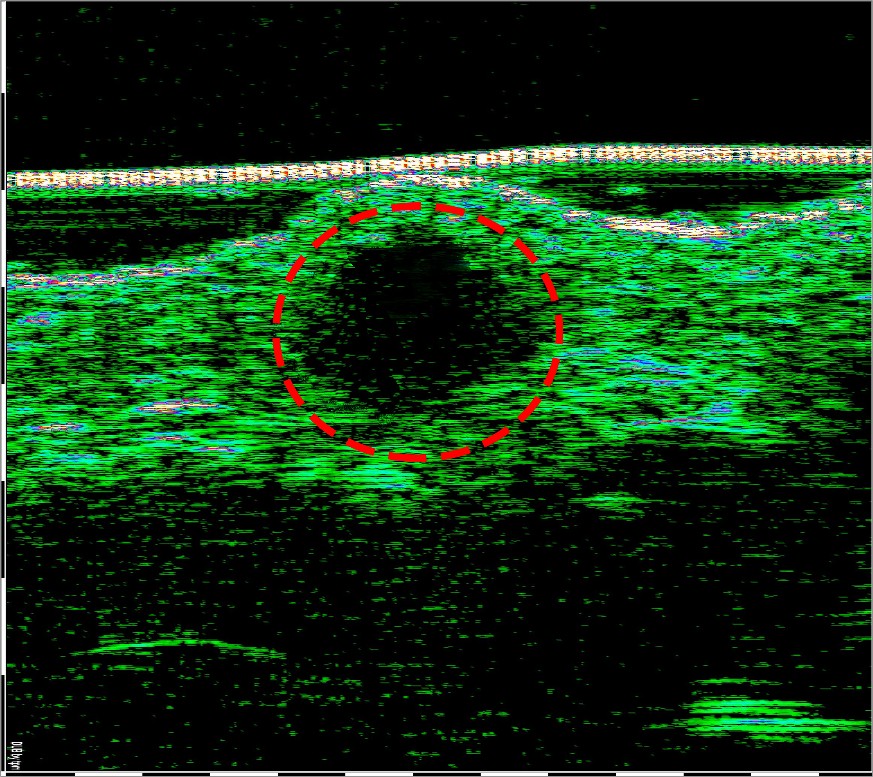

Επιπλοκή μετά από έγχυση filler. Κοκκίωμα προκαλούμενο από ξένο προς το δέρμα σώμα.

Ταυτόχρονα, παρόλα τα οφέλη των δερματικών fillers, υπάρχει πάντα η πιθανότητα παρενεργειών και επιπλοκών.

Οι πρώιμες επιπλοκές εμφανίζονται με τη μορφή φλεγμονωδών και αλλεργικών αντιδράσεων, μετατόπισης fillers, συμπίεσης αιμοφόρων αγγείων και διείσδυσης του filler σε αρτηριακά αγγεία, με τη μορφή αποστημάτων και νέκρωσης.

Οι όψιμες επιπλοκές εμφανίζονται αρκετούς μήνες ή και χρόνια μετά την έγχυση του filler με τη μορφή μη απορροφημένων οζιδιακών αποθέσεων, κοκκιωμάτων ξένων σωμάτων, σκληρωτικών περιοχών και ινωδών καψουλών γύρω από το filler.

Η απεικόνιση με υπερήχους υψηλής συχνότητας επιτρέπει την παρακολούθηση των σταδίων βιοαποικοδόμησης του filler, των μετατοπίσεων των fillers, καθώς και των παρενεργειών και επιπλοκών των fillers.

-Επιπλοκή, κοκκίωμα μετά από έγχυση Filler